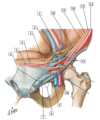

#1 - testicular vessels and genital branch of the genitofemoral nerve

#2 - inferior epigastric vessels

#3 - medial umbilical ligament

#4 - retus abdominis mucle

#5 - median umbilical ligament

#6 - superficial inguinal rings

#7 - intercrural fibers

#8 - inguinal ligament

#9 - cremasteric muscle

#10 - spermatic cord

#11 - internal spermatic fascia (from transversalis fascia at deep inguinal ring)

#12 - external abdominal oblique muscle

#13 - internal abdominal oblique muscle

#14 - transversus abdominis muscle

#15 - transversalis fascia

#16 - peritoneum